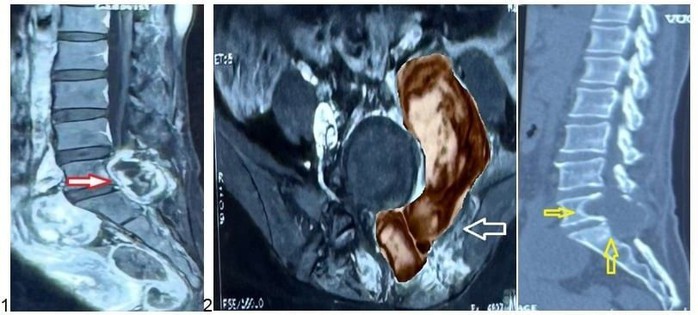

Kết quả chụp MRI cho thấy khối u kích thước lớn xâm lấn các cấu trúc lân cận và gây hủy xương vùng cột sống cùng

BS CKII Lê Điền Sơn - Phó trưởng Khoa Ngoại Thần kinh, Bệnh viện Nhân dân 115 - chia sẻ: "Khối u nằm đúng vị trí phẫu thuật cũ, có hình ảnh phát triển bất thường. Do đó, chúng tôi nghĩ nhiều đến khả năng u tái phát, thậm chí có thể mang tính chất ác tính".

Xác định đây là một khối u có kích thước lớn, giàu mạch máu nuôi và đã xâm lấn các tổ chức xung quanh, ê-kíp Khoa Ngoại Thần kinh đã chủ động hội chẩn đa chuyên khoa với đơn vị DSA và chuyên khoa Ngoại Niệu.